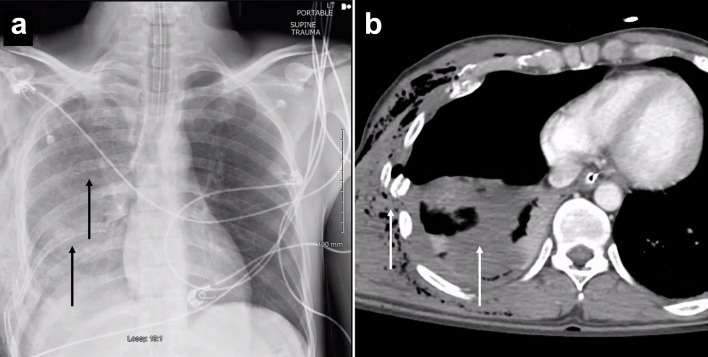

对于多发性肋骨骨折或胸部外翻的患者来说,肋骨固定是一种值得推荐的干预措施,可改善呼吸急促、显著减轻疼痛并缩短住院时间。在此,我们报告了一名胸内肋骨固定术后出现肺水肿患者的独特且极其罕见的发现。一名有酗酒史的 32 岁男性在一次车祸后被送往急诊科创伤室。计算机断层扫描(CT)显示患者右侧血气胸,第四至第九根肋骨骨折并移位。随后使用钛合金 RibFix 固定桥对右侧第五和第六根肋骨进行了固定,并沿肋骨后表面植入胸腔内。术后第 11 天,患者出现肺水肿,在 CT 引导下将引流导管置入积水处。患者接受了为期 3 天的组织浆肌酶原激活剂(tPA)和 DNase 治疗。术后第 15 天,复查 CT 扫描显示,患者的肺水肿明显好转,有证据表明脓肿已经消退。总共 7 天后,患者停用了抗生素,并于术后第 20 天出院。本病例报告为胸腔内肋骨固定术并发症的处理提供了信息。

Rib plating is a recommended intervention for patients with multiple rib fractures or flail chest to improve shortness of breath, significantly reduce pain, and shorten the length of hospital stay. Here, we report a unique and extremely rare finding in a patient with empyema following intrathoracic rib fixation. A 32-year-old male with a history of alcohol use disorder presented to the emergency department trauma bay after a motor vehicle accident. Computed tomography (CT) showed right hemopneumothorax and fourth to ninth rib fractures with displacement. The right fifth and sixth ribs were then plated using a titanium RibFix bridge, implanted intrathoracically along the posterior surface of the ribs. On postoperative day 11, the patient developed an empyema and a CT-guided drainage catheter was placed into the collection. The patient was given a 3-day course of tissue plasminogen activator (tPA) and DNase for the treatment of his empyema. On postoperative day 15, a repeat CT scan demonstrated significant improvement in the empyema with evidence of abscess resolution. Antibiotics were discontinued after a total of 7 days and the patient was discharged on postoperative day 20. This case report contributes information to the management of complications in intrathoracic rib fixation.